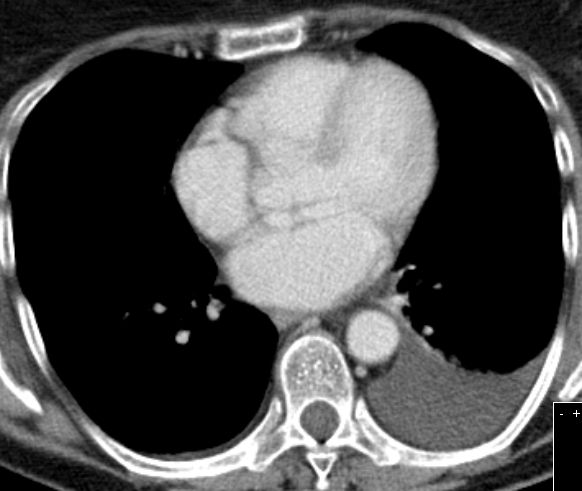

Perikard - Karzinose | |||

CT |